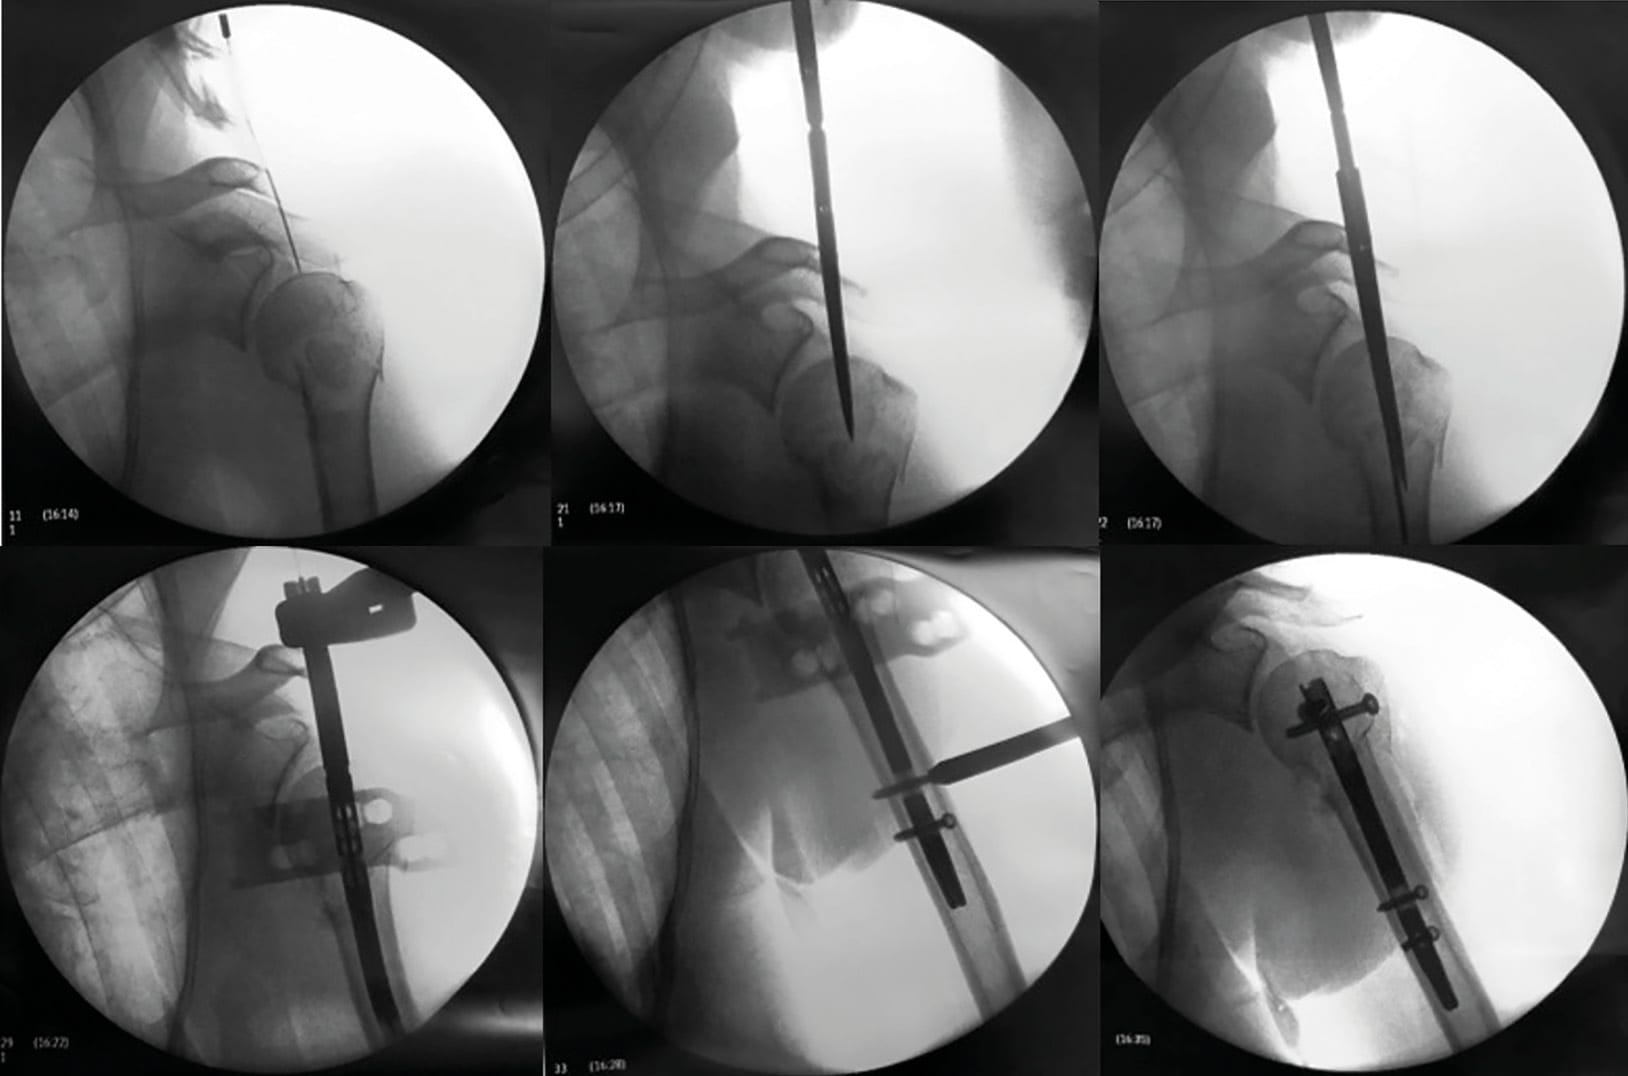

Patients are placed in the sitting position and the C-arm image intensifier control, approaching from the contralateral side of the table to visualize the proximal humerus, is placed orthogonal to the shoulder (Figure 2). The goal of the minimally invasive percutaneous technique is to enter the cartilage of the humeral head (entering the supraspinatus muscle fibers, not the tendon) before entering the medullary canal of the diaphysis to align the head fragment and the shaft, and then to derotate the diaphysis (Figure 3).

Under C-arm guidance, optimizing the starting point of the nail in the humeral head was essential to obtain anatomical reduction.[46] Riemer BL, D'Ambrosia R, Kellam JF, Butterfield SL, Burke CJ. The anterior acromial approach for antegrade intramedullary nailing of the humeral diaphysis. Orthopedics. 1993;16(11):1219–1223. The entry point of a straight nail must be located approximately 10mm posterior and medial to the bicipital groove.[14], Dilisio MF, Nowinski RJ, Hatzidakis AM, Fehringer EV. Intramedullary nailing of the proximal humerus: evolution, technique, and results. J Shoulder Elbow Surg. 2016;25(5):e130–8. doi:10.1016/j.jse.2015.11.016[26], Jeong J, Jung H-W. Optimizing intramedullary entry location on the proximal humerus based on variations of neck-shaft angle. J Shoulder Elbow Surg. 2015;24(9):1386–1390. doi:10.1016/j.jse.2015.01.016[29], Knierim AE, Bollinger AJ, Wirth MA, Fehringer EV. Short, locked humeral nailing via Neviaser portal: an anatomic study. J Orthop Trauma. 2013 Feb;27(2):63–67. doi:10.1097/BOT.0b013e31825194ad[38], Noda M, Saegusa Y, Maeda T. Does the location of the entry point affect the reduction of proximal humeral fractures? A cadaveric study. Injury. 2011;42 Suppl 4:S35–8. doi:10.1016/S0020-1383(11)70010-9[42] Park J-Y, Pandher DS, Chun J-Y, Md STL. Antegrade humeral nailing through the rotator cuff interval: a new entry portal. J Orthop Trauma. 2008 Jul;22(6):419–425. doi:10.1097/BOT.0b013e318173f751 Once proper entry portal is defined, a cannulated bone awl is used for entry and joystick the humeral head under fluoroscopic guidance. A guide-wire is placed through the bone awl into the humeral head. After manipulation of the arm to obtain the best alignment between the epiphysis and the diaphysis, the guide-wire is then advanced inside the humeral shaft.

Once adequate guide pin placement is achieved, a 9-mm hole is created in the humeral head using a cannulated reamer. The cannulated nail is placed over the guide wire, inserted at the apex of the humeral head, and then inside the diaphysis, providing appropriate fracture alignment. The arm is placed in neutral rotation to achieve adequate derotation of the humeral diaphysis, whereas adequate rotation of the nail is achieved with the assistance of an external jig aligned with the forearm (Figure 4).